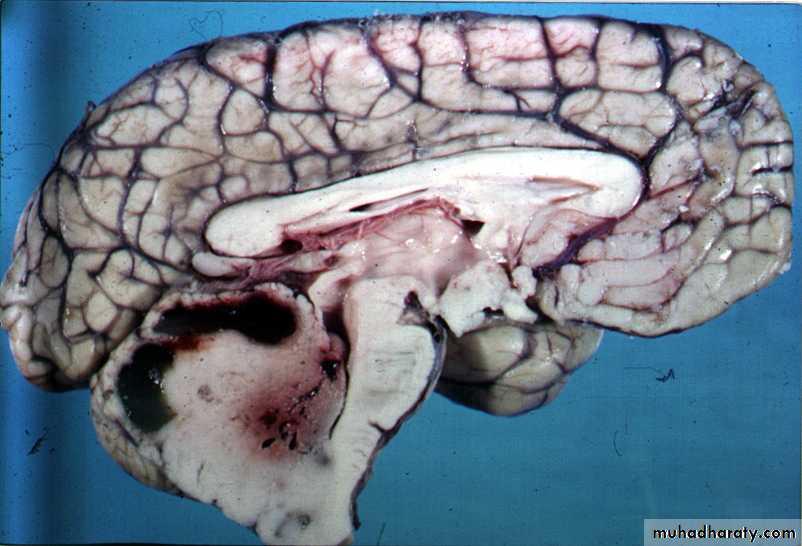

MEDULLOBLASTOMA

CEREBELLUM AFTER SURGERY FOR MB